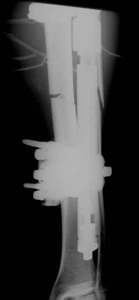

Das Infektionsrisiko beim Verfahrenswechsel ist gering, wenn dieser

innerhalb von 2-3 Wochen erfolgt.

Grundsätzlich müssen dem Patienten die Alternativverfahren

Dynamischer Fixateur und Verriegelungsnagel angeboten werden. Beim

Verfahrenswechsel bevorzugen wir den Titannagel T2, da uns bei diesem

Nagel das Infektionsrisiko geringer erscheint. Die Ausheilungszeit

ist bei beiden Verfahren zwar gleichwertig, aber der T2 Nagel wird

von den Patieten besser akzeptiert.